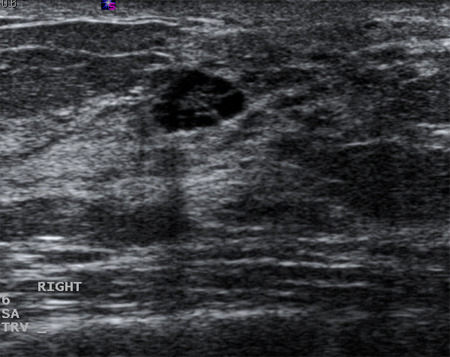

Os cistos que persistem ou não se resolvem completamente com a aspiração devem ser submetidos a biópsia para descartar a malignidade. Da mesma forma, a biópsia deve ser considerada em cistos complexos ou naqueles com elementos sólidos. As características sonográficas podem classificar uma massa sólida tanto como "provavelmente benigna" quanto como "suspeita". Massas lisas, ovais, lobuladas, com margens claramente definidas e mais largas que compridas geralmente são benignas (por exemplo, fibroadenoma). Se a massa é irregular, heterogênea, tem margens espiculadas ou pouco definidas, é mais comprida que larga, ela é considerada "suspeita" para malignidade, e deve ser realizada uma biópsia.[Figure caption and citation for the preceding image starts]: Imagem ultrassonográfica de um carcinoma complexoCortesia do Dr. Lane Roland, Universidade de Louisville; usado com permissão [Citation ends].

[Figure caption and citation for the preceding image starts]: Imagem ultrassonográfica de um carcinoma invasivoCortesia do Dr. Lane Roland, Universidade de Louisville; usado com permissão [Citation ends].